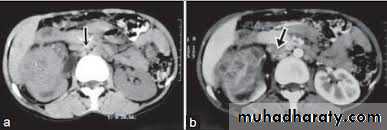

Acquired renal cystic disease (ARCD)

ARCD is cystic degenerative disease of the kidney with greater than 5 cysts visualized on CT scan. By definition, this is an acquired condition, in contrast to adult polycystic kidney disease (ADPKD), which is inherited (in an autosomal dominant fashion). It is predominantly associated with chronic and end-stage renal failure (originally, it was thought to specifically affect patients on hemodialysis).It is clinically important because it may cause pain or hematuria and is associated with the development of benign and malignant renal tumors.

Approximately one-third of patients develop ARCD after 3 years of dialysis. The male-to-female ratio is 2:1.